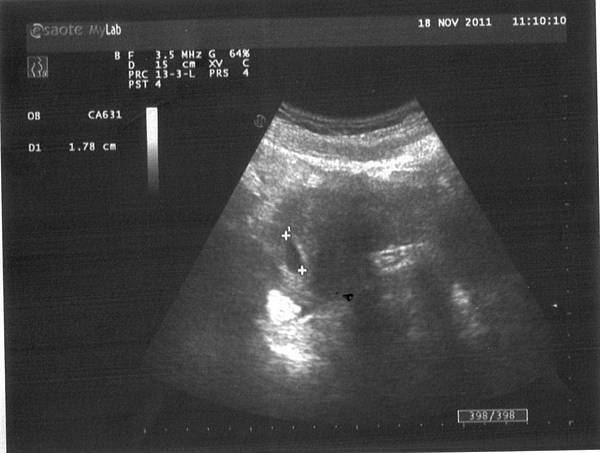

照超音波的過程也很輕率,醫生壓壓我的肚子,

就說「在右下腹,大概五週,兩個禮拜後來看有沒有心跳」,

然後就結束了=___=

不過看到肚子裡有小生命真是好奇妙

分明就是顆小肉球啊你~~